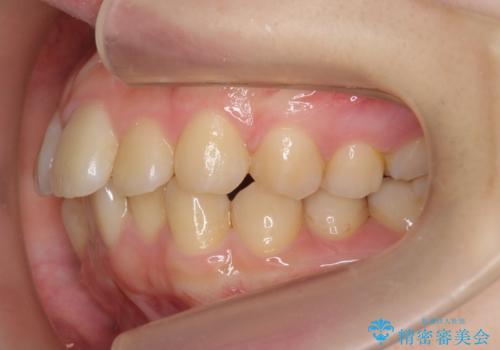

左右とも奥歯のがたつきがあり、左奥はすれ違っていました。

また、右奥は反対咬合になっていました。

インビザライン治療は主に奥歯のかみ合わせが大きな問題がない場合は特に問題なく終了しますが、今回のケースのように奥歯のかみ合わせが悪い場合、しっかり治らないことがあります。

患者様が気づかない範囲で妥協して終わるということをせず、しっかり奥歯に部分矯正を用いて大きな問題を解決してからインビザライン治療に入りました。

奥歯のワイヤー部分矯正は位置的に人から気づかれることはないと思います。

奥歯までしっかり咬ませたい場合、矯正医を選ぶ場合は注意が必要です。